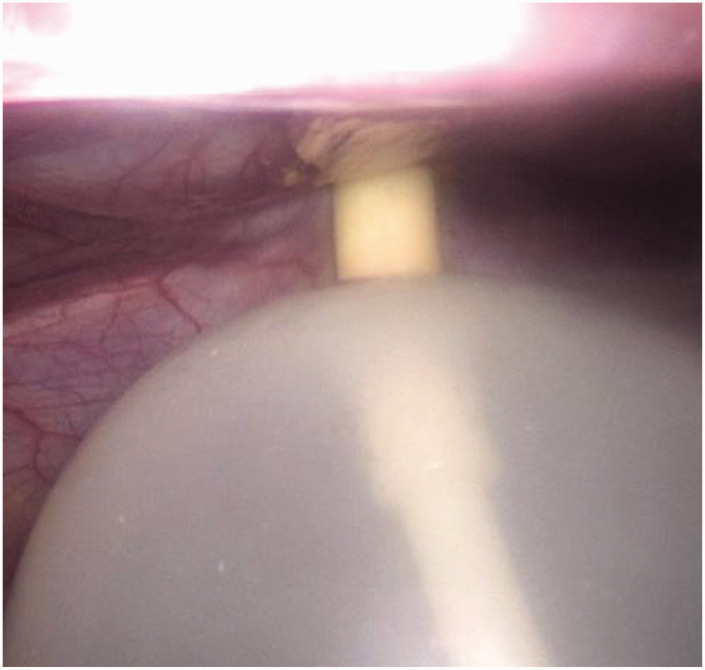

目的腹腔镜手术已广泛应用于外科手术。套管针部位疝是腹腔镜手术中一种独特的并发症。封闭套管针部位缺损可能是防止套管针部位疝形成的重要组成部分。我们报告一种新的,简单的,安全的技术来关闭端口部位的伤口。这种易于操作的工具只需要一个气囊导管,并涉及一个安全的程序。方法回顾性分析长江大学第一附属医院疝外科于2022年1月至2024年7月收治的55例(其中腹腔镜腹股沟疝54例,阑尾炎1例)。用直角牵引器牵拉皮肤和皮下组织后,用充气球囊导管向上提起腹膜筋膜。套管针部位在直视下闭合,无并发症报道。结果54例患者中55个部位采用套管针缝合术,无不良反应发生。只需要一个球囊导管,没有其他组织损伤的报道。这项技术很容易学习和操作。中位随访15个月无套管针部位疝或腹部器官损伤报告。结论套管针缝合术是一种操作简单、安全、经济的方法。

ObjectiveLaparoscopic ports have been used in many surgical procedures. Trocar-site hernias are a unique complication in laparoscopic surgeries. Closing the trocar-site defect could be an essential part of trocar-site closure for preventing trocar-site hernia formation. We report a new, simple, and safe-to-perform technique to close port-site wounds. This easy-to-manipulate tool only requires a balloon catheter and involves a safe procedure.MethodsIn this retrospective study, 55 port-site closure cases (54 cases of laparoscopic inguinal hernias and 1 case of appendicitis) were enrolled from January 2022 to July 2024 in the Department of Hernia Surgery at the First Affiliated Hospital of Yangtze University. An inflatable balloon catheter was used in the upward direction to lift the peritoneum fascia after the skin and subcutaneous tissue were retracted with a right-angled retractor. The trocar site was closed under direct vision, and no complications were reported.ResultsThe trocar-site closure technique was used in 55 port sites among 54 patients, and no adverse events occurred. Only a balloon catheter was required, and no additional tissue trauma was reported. This technique is easy to learn and manipulate. No trocar-site hernia or abdominal organ injury was reported at the median follow-up of 15 months.ConclusionsThe trocar-site closure technique is a simple-to-manipulate, safe, and cost-effective approach.